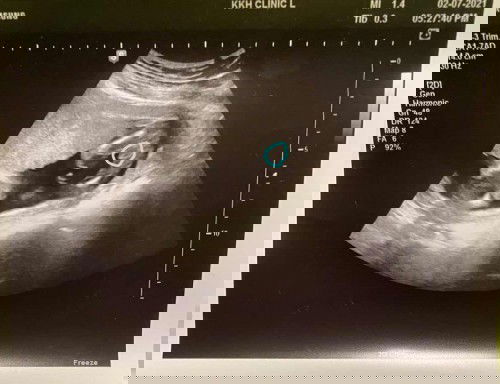

Boy or girl?

Hi everyone. Just had my week 16 ultrasound scan today. Gynae said I’m most likely having a boy based on the scan but she says we can be more sure after the next appt in 4 weeks. I just wanted to get your thoughts though. Anyone else have/ has had a baby boy and they had a similar-looking scan at 16 weeks? :) Thanks!